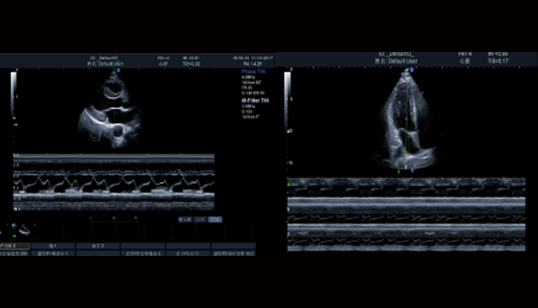

Heart imaging: 心脏成像

高清心脏M型成像

• 对于外形或位置异常的心脏,都能保持M型线与解剖结构垂直。三线M型在同一个心动周期内准确获得心脏组织数据。

TDI组织多普勒成像

• 用于评估心肌活动的方向和时间,显示血管壁运动和心脏组织运动速度

SRI应变率成像

• 通过对图像进行彩色编码,可用于评价心室整体和局部功能,大大增强了心脏检测的临床应用。